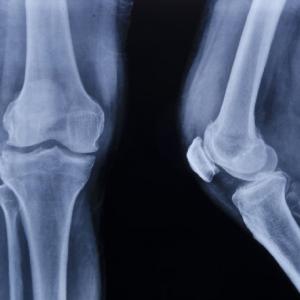

Изследователите не са измервали плътността на костите, но натоварването при стъпването на земята било значително. Когато то се комбинира с напрежението на мускулите, било достатъчно за укрепване на костите.

Според д-р Монтгомъри ефектът от подскоците увеличава костната плътност с 2% годишно. Повече от 20 на сто от жените, навършили 50 години, имат остеопороза.